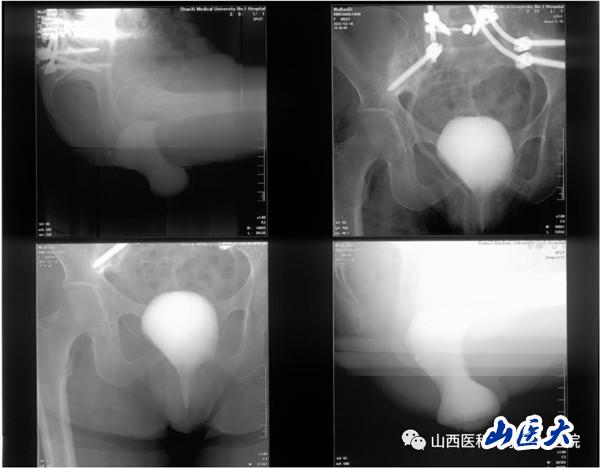

患者女性,62岁,盆腔脏器脱垂合并骶骨缺损,近年来辗转北京及省内各大医院寻求外科治疗,但均未能如愿。

这8例疑难复杂病例是由泌尿外科尿控及盆底疾病专业组茹峰、任力娟、蔺学铭、赵长剑、张超等精心筹划收集的,涵盖盆腔脏器脱垂合并骶骨缺损、放疗术后盆腔脏器脱垂合并SUI等。